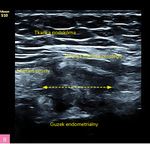

Rycina 1A, B. Obraz ultrasonograficzny zmiany endometrialnej powłok brzucha z typowymi spikularnymi brzegami (materiał własny autorki)

Charakterystyka wszczepów endometrialnych powłok brzucha (tab. 2; ryc. 1, 2):

- zmiany w większości hipoechogeniczne i heterogenne

- zmiany zwykle wykazują słabe unaczynienie

- średnica zmian wynosi między 5 mm a 5 cm, chociaż mogą osiągać znaczne rozmiary

- zmiany mają charakterystyczny spikularny (naciekający) obwód lub miejscowo nieregularny margines

- małe torbielowate obszary, głównie położone obwodowo – obraz drobnych torbieli krwotocznych, dające cień akustyczny

- obwodowe cechy włóknienia – hiperechogenna otoczka wokół guza.